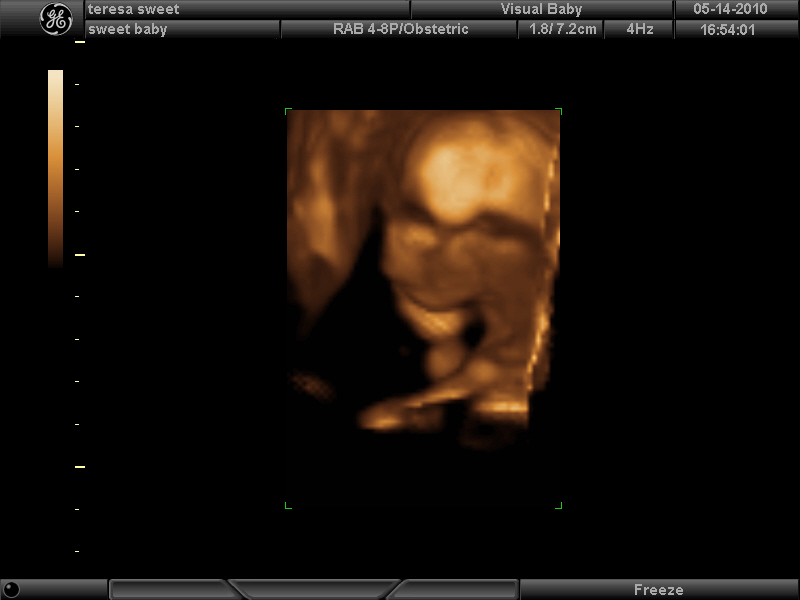

Here’s a few photos in 3D. I’m 17 wks now.

awwwww another boy yay! what a cute name for him, too 🙂 congratulations! how exciting. the 3d ultrasounds are amazing huh?! i noticed in one pic he had his hand under his chin. lol jacob was sleeping during an ultrasound also w his fist under his chin too and then the next day i woke up and realized that’s how i sleep 🙂 aw he sleeps like his mommy! i will be catching up with you soon (i hope!) lol once he decides to make his debut so you can take his pix. in the mean time we are certainly enjoying our maternity pix-thank you again xo